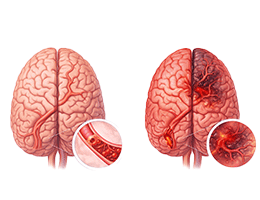

뇌졸중 (Stroke)

뇌출혈 (ntracerebral Hemorrhage)